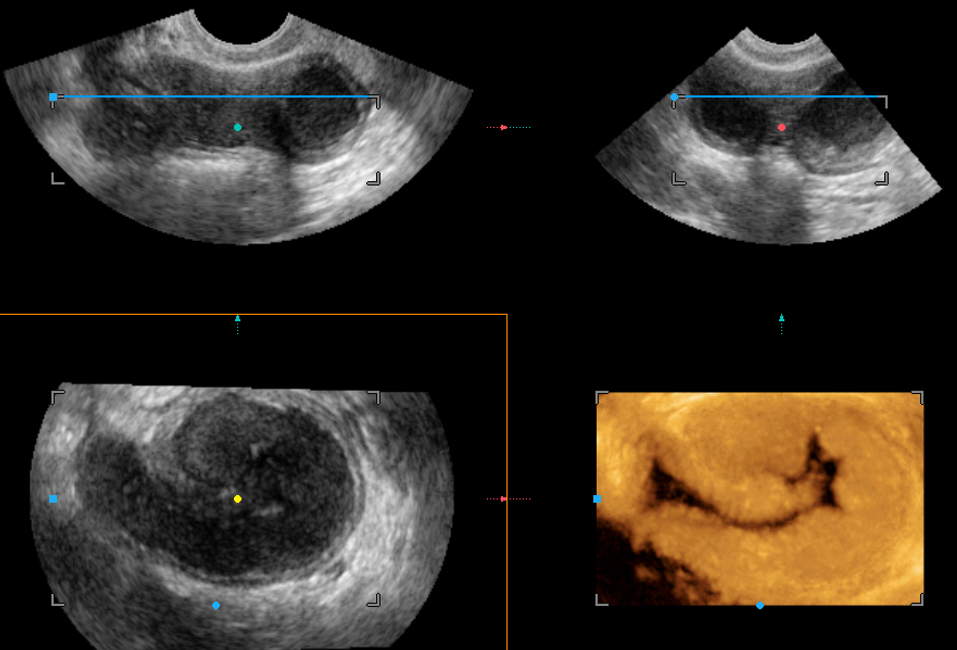

Современные экспертные УЗИ сканеры дают возможность проводить исследования всех органов в 3D. Это позволяет, используя полученный массив данных, получать диагностические сечения в любой плоскости, недоступной для обычного 2D УЗИ. Наиболее интересной является фронтальная. Например, визуализация полости матки. Диагностическая возможность выявления пороков развития превосходит все другие методы (рентгеновские и МРТ). Метод также позволяет уточнить положение ВМК (спирали) в полости матки, расположение миоматозных узлов, расположение плодного яйца на малых сроках, полипов. Сегодня современное экспертное ультразвуковое исследование невозможно без использования 3D УЗИ.